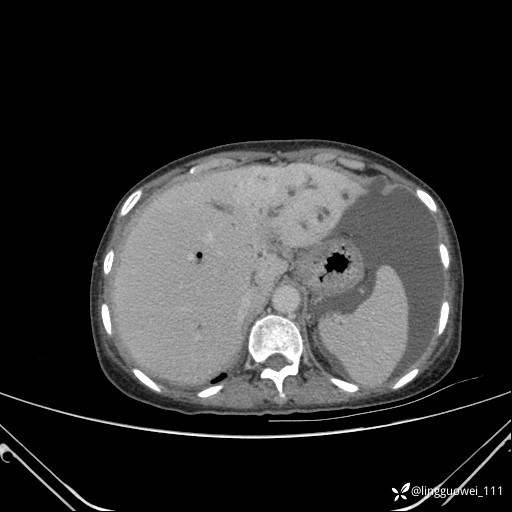

病例女,65岁,门诊行胃肠镜检查后,说腹胀入院检查,CT能发现病因吗?已公布结果

主诉:门诊行胃肠镜检查后,诉腹胀,入院检查,肝有病变吗?腹膜及腹腔的表现有特征性吗?

平扫: